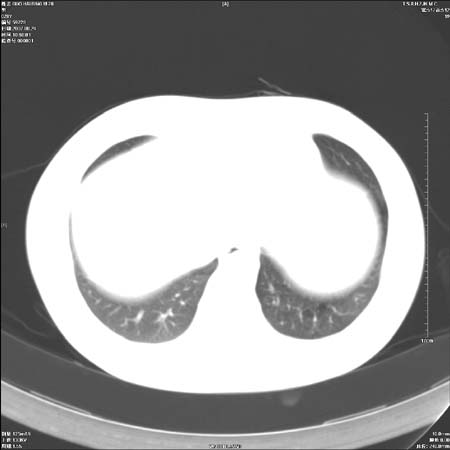

直接下肺癌诊断还太早,病灶较大,估计5cm以上,但阻塞性改变及对临近纵隔及支气管侵犯不明显,密度较均匀,弓旁见一单个淋巴结,需要排除炎症性肿块及腺瘤,平滑肌瘤等。

左肺中心型肺癌并纵隔淋巴结转移!考虑为小细胞肺癌,没有手术机会了,只能进行放化了,疗效不错,但极易复发。没办法,现在肿瘤年轻化越来越明显了。